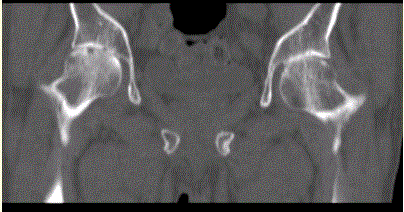

问题 患者女,53岁,双髋关节痛。双髋关节CT平扫冠状重组影像如下图。 对定性诊断有价值的征像包括

选项 A.双髋关节间隙对称性均匀狭窄 B.右侧股骨头关节面可见小囊状透亮影 C.双髋关节骨质疏松 D.双髋关节未见骨赘 E.双髋关节囊肿胀 F.双髋关节面下无骨质硬化

答案 ACDF